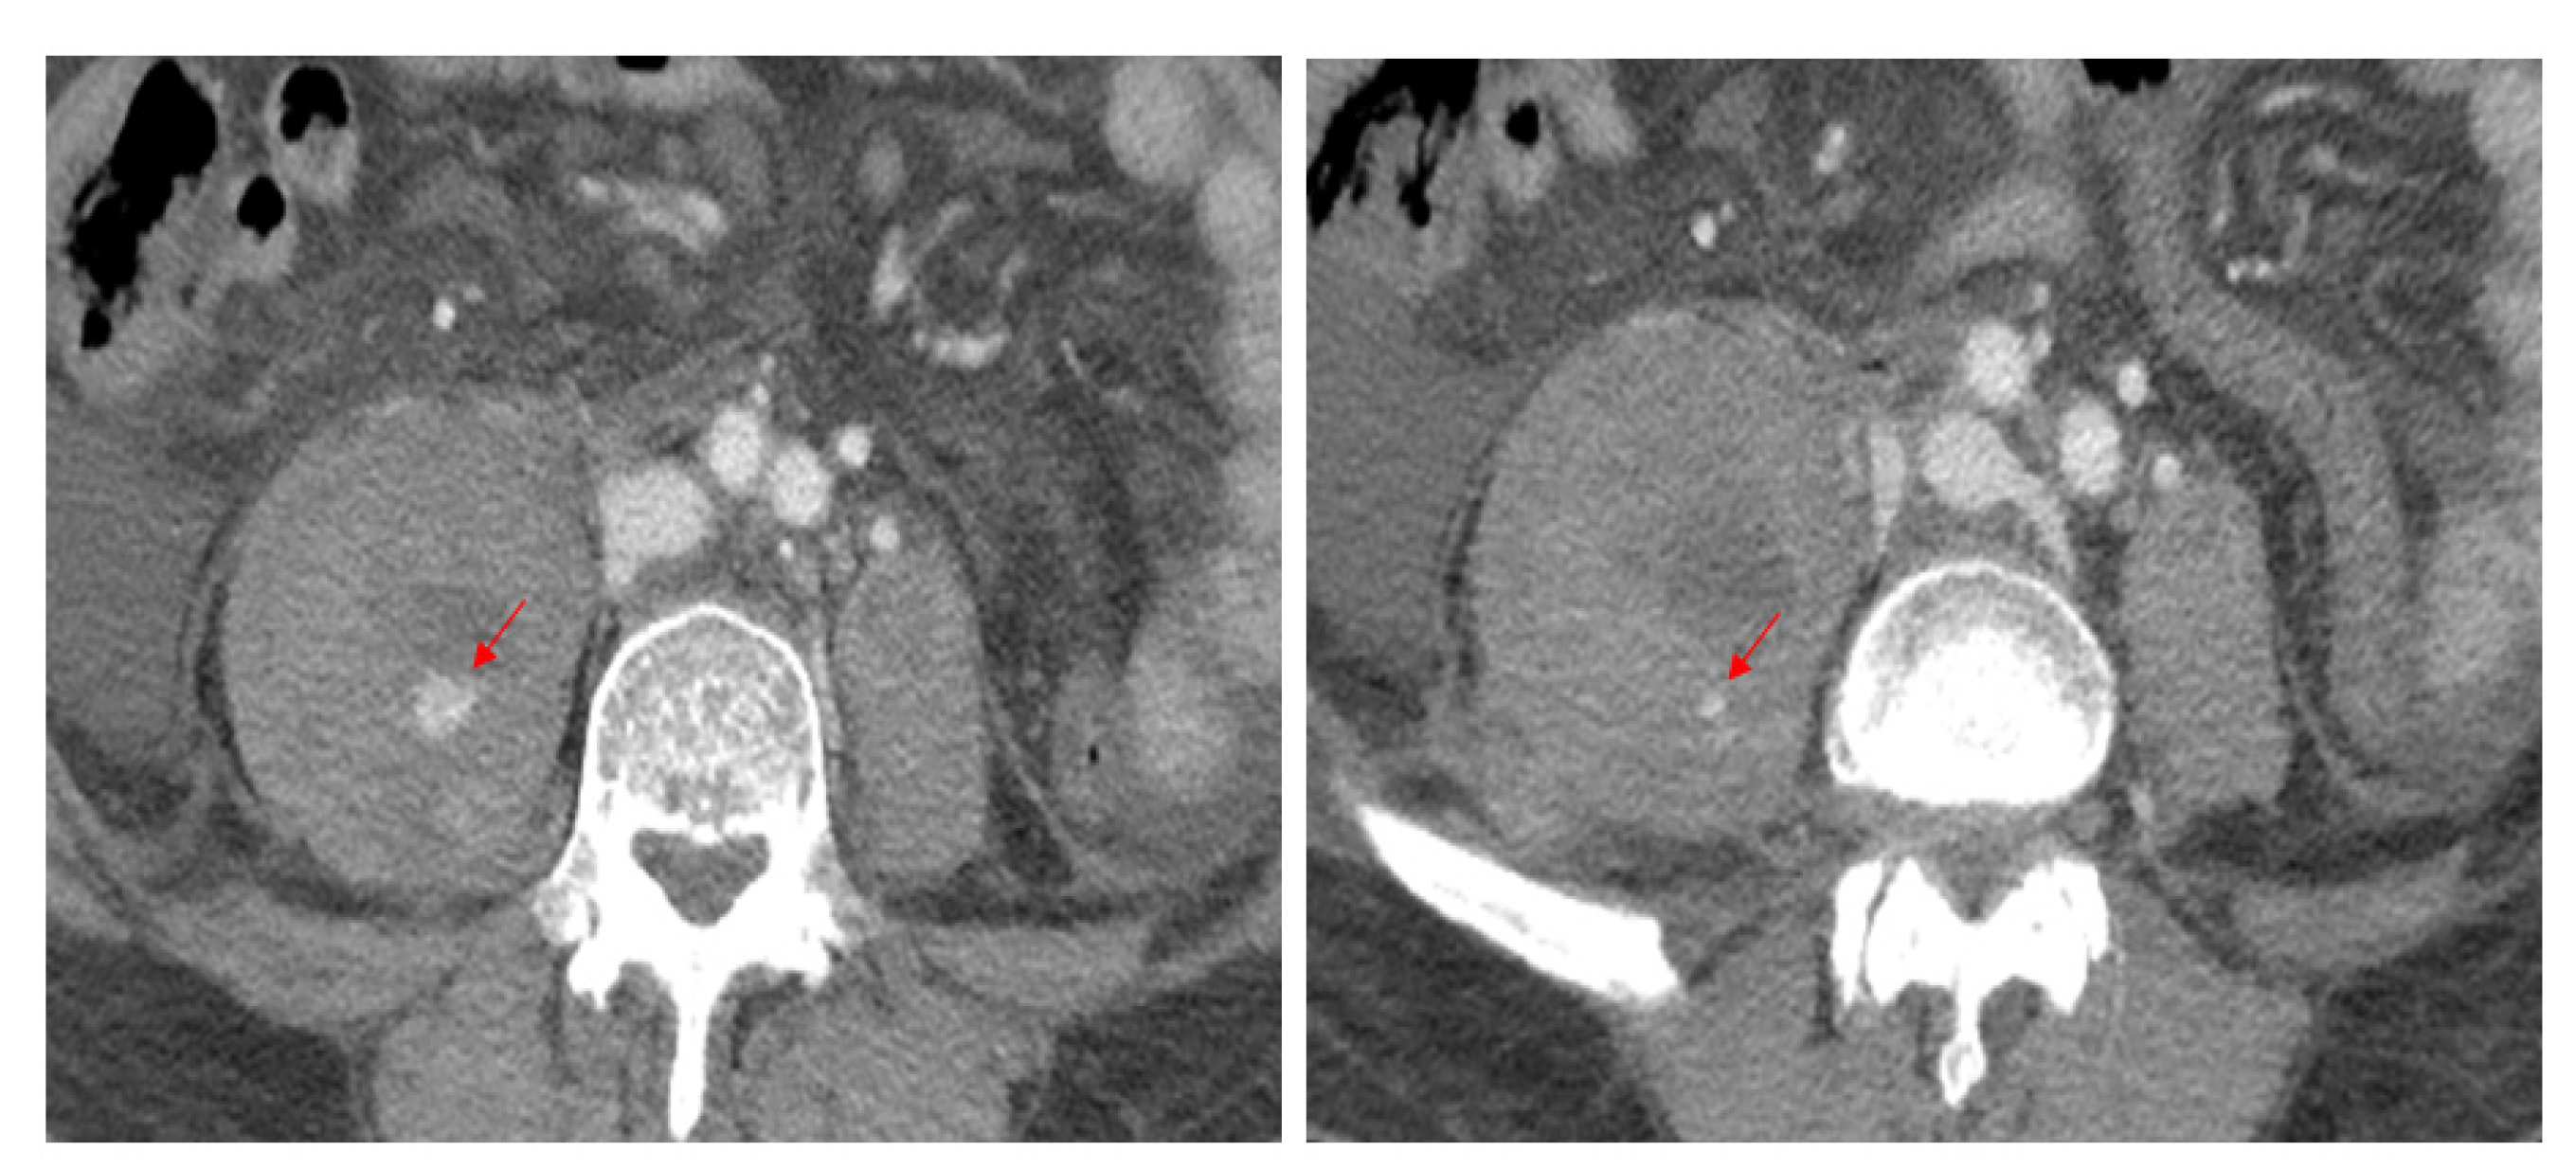

Considering the patient’s low hemoglobin level, an emergent computed tomography (CT) scan of the abdomen and lumbar spine was performed to exclude hemorrhages. Enhanced CT scans revealed a massive psoas hematoma, measuring 10 × 7 × 11 cm, extending from L2 to L5. Contrast dye leakage into the hematoma due to active bleeding from the injured segmental artery was detected (Figure 1). Magnetic resonance imaging (MRI) and CT scan of the lumbar spine revealed a stable osteoporotic VCF at L3 and an old compression fracture at L1, where vertebroplasty had already been performed (Figure 2). DEXA bone mineral densitometry was performed and showed severe osteoporosis (mean T-score of femur neck and spine: −3.6).

Figure 1.

Contrast-enhanced CT scans reveal high attenuation, indicating active bleeding (arrows) from the right second and third lumbar arteries within the hematoma.